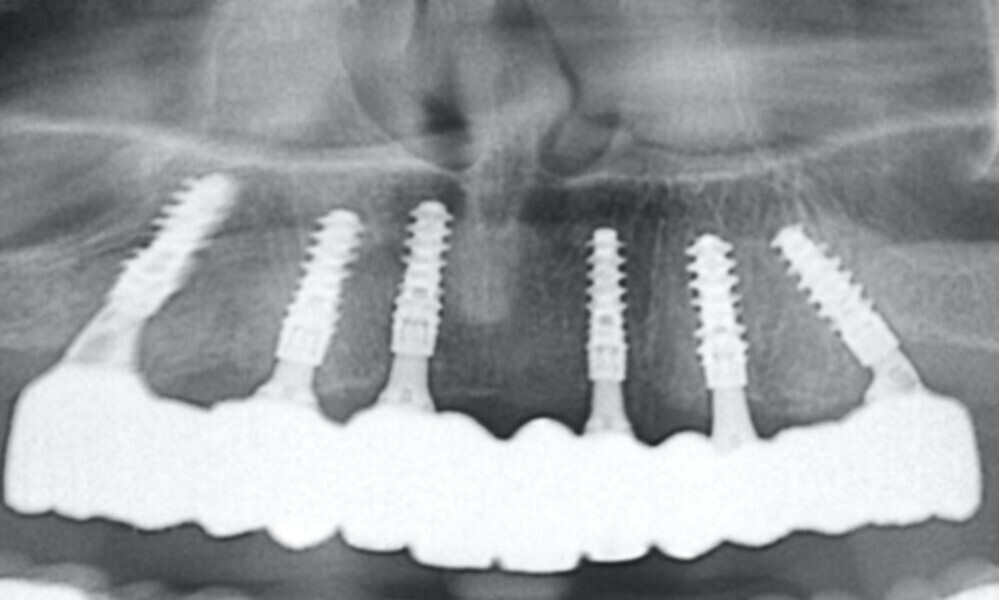

The delivery of the final prosthesis was then performed, and the aesthetics, occlusion and function were verified (Figs. 51–55). The panoramic control radiograph showed that all measurements were within expected ranges (Fig. 56).